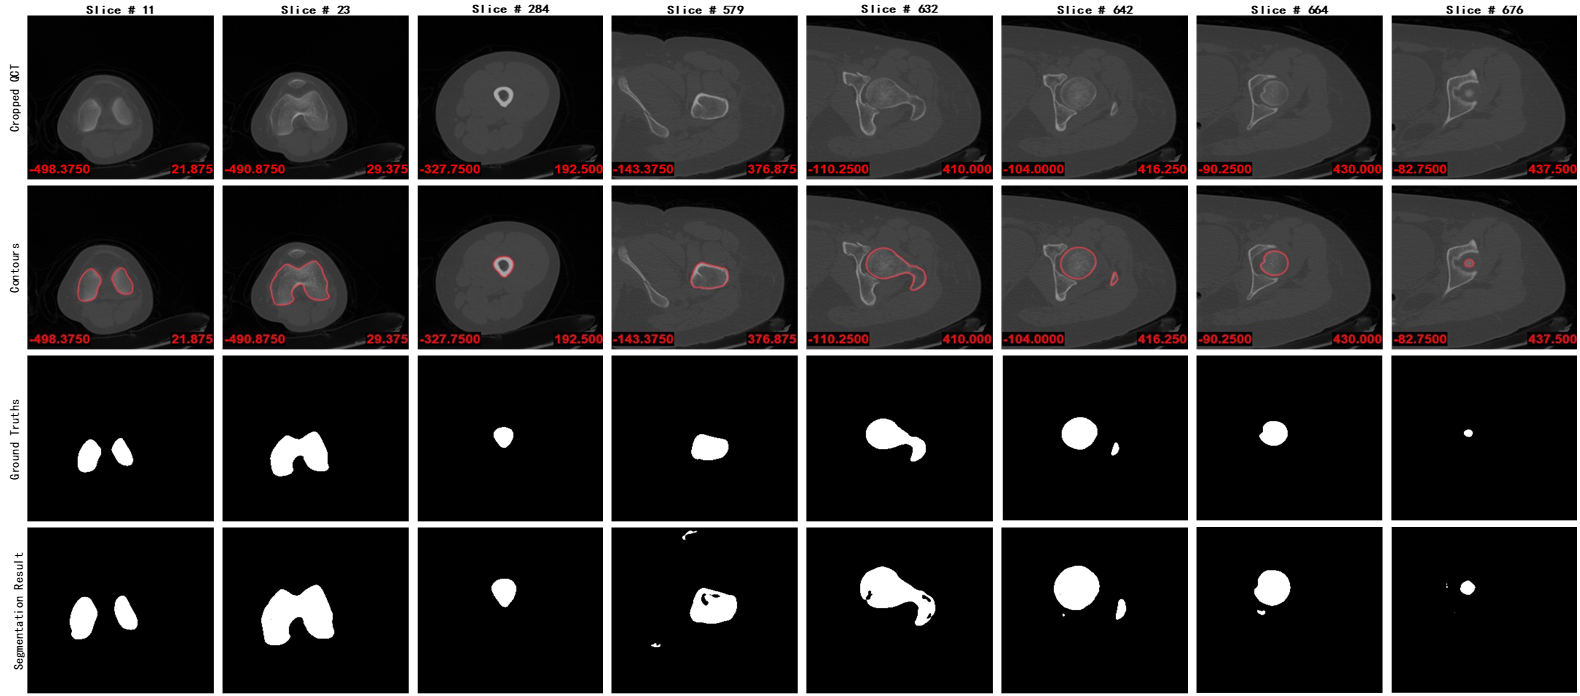

我们标注了来自20名不同患者的左股骨的作为数据集进行训练,并用一组左股骨序列图片作为测试集,得出最终结果如下图所示:

从上至下每一行分别为股骨CT图片、股骨真实轮廓线、人工标注股骨区域、模型预测结果,最终模型预测的精度能够达到98.56±0.02,为了提高模型精度,后期会股骨远端和近端分别训练,以达到更好的分割效果。